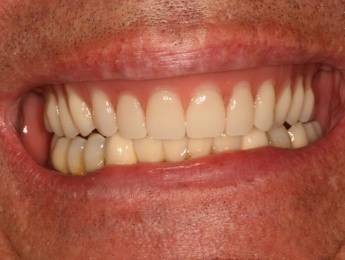

Ennek a kedves hölgynek 20 éves álmát váltottuk valóra. 20 évig hordott kivehető fogsorokat. 12 implantátum beültetése után alsó és felső fixen rögzített hidakat készítettünk. Nincs többé kivehető - evéskor, beszéd közben - elmozduló fogsor. Javult a rágási hatékonyság is, amely az egészséges táplálkozás szempontjából is nagyon fontos tényező.